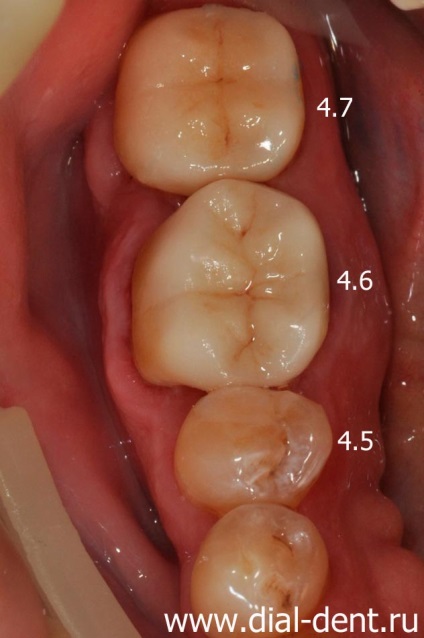

Soluție: au fost tratate canale sub microscop. tratarea cariilor, restaurate umpluturile dinti si coroane (dinti 1,4, 4,5 - obturațiilor ușoare, 1.5, 1.6, 4.6, 4.7 - 1.7 coroane ceramice -. cape de coroane și metaloceramice).

- Înlocuirea plombe vechi în dinți de 1,5, 1,6, 4,6, 4,7.

- Prostetice 1.5, 1.6, 4.6, 4.7 coroane ceramice.

Tratamentul cariilor si inlocuirea obturatiilor vechi efectuate KV prosthodontist Verzilov. Îndepărtarea tuturor țesuturilor cariat este realizată cu zoom-ul optic, care ajută la dentist pentru a salva un maxim de structura sănătoasă a dintelui și să se pregătească cu grijă cavitatea de etanșare. Dinții 1.4 și 4.5 sigiliilor de lumină restaurate. umpluturi vechi în dinți 1.6, 1.5, 4.6 și 4.7 se înlocuiesc cu noi umpluturi fotopolimerizabil.

Patru dinți (1.6, 1.5, 4.6, 4.7) vor fi acoperite cu coroane ceramice, care le va consolida și de a restabili funcția de mestecat și aspectul.

Dinții 1.5, 1.6, 4.6, 4.7 - coroane ceramice.